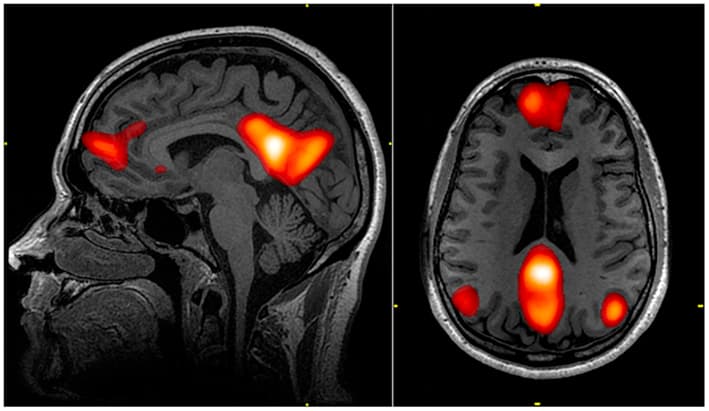

In neuroscience, the default mode network (DMN), also known as the default network, default state network, or anatomically the medial frontoparietal network (M-FPN), is a large-scale brain network primarily composed of the dorsal medial prefrontal cortex, posterior cingulate cortex, precuneus and angular gyrus. It is best known for being active when a person is not focused on the outside world and the brain is at wakeful rest, such as during daydreaming and mind-wandering. It can also be active during detailed thoughts related to external task performance. Other times that the DMN is active include when the individual is thinking about others, thinking about themselves, remembering the past, and planning for the future. The DMN was originally noticed to be deactivated in certain goal-oriented tasks and was sometimes referred to as the task-negative network, in contrast with the task-positive network. This nomenclature is now widely considered misleading, because the network can be active in internal goal-oriented and conceptual cognitive tasks. The DMN has been shown to be negatively correlated with other networks in the brain such as attention networks. Evidence has pointed to disruptions in the DMN of people with Alzheimer's disease and autism spectrum disorder. Hans Berger, the inventor of the electroencephalogram, was the first to propose the idea that the brain is constantly busy. In a series of papers published in 1929, he showed that the electrical oscillations detected by his device do not cease even when the subject is at rest. However, his ideas were not taken seriously, and a general perception formed among neurologists that only when a focused activity is performed does the brain (or a part of the brain) become active. But in the 1950s, Louis Sokoloff and his colleagues noticed that metabolism in the brain stayed the same when a person went from a resting state to performing effortful math problems suggesting active metabolism in the brain must also be happening during rest. In the 1970s, David H.